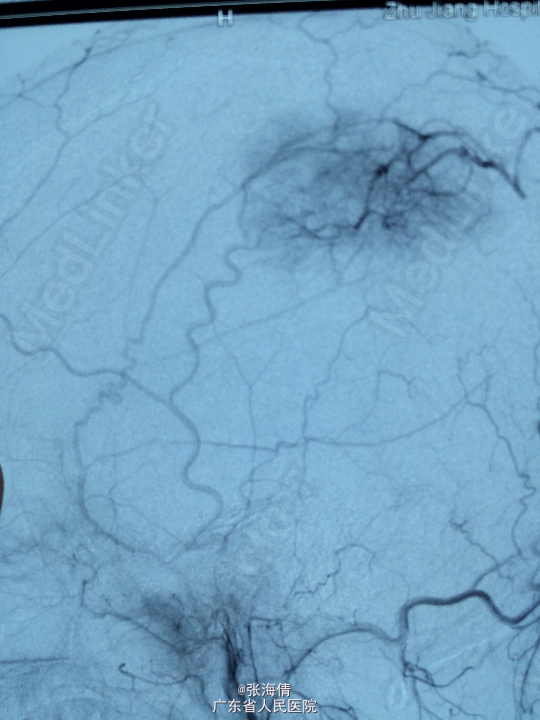

诊断:脑膜瘤 处理:先予DSA以明确肿瘤供血情况,术中脑膜瘤供血丰富,用PVA颗粒超选到供血动脉将其闭塞。后再择期在气管全麻下行脑膜瘤切除术。

术后病理提示:脑膜瘤,WHO I级,瘤组织浸润脑组织。免疫组化:Ki一67(<1%)(+),CK(一),GFAP(一),Vimentin(+),EMA(+),P53(一),ER(一),PR(一)。 讨论:脑膜瘤首选方法为手术切除,手术切除脑膜瘤是最有效的治疗手段,但是由于其供血经常较为丰富,故可先行介入栓塞供血动脉后再行切除,这样可以降低手术风险和手术难度,改善患者手术预后。